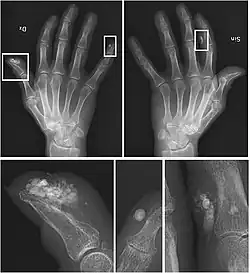

CREST syndrome (calcinosis and sclerodactyly)

X-rays showing calcinosis in a woman with CREST syndrome

Calcinosis

CREST causes thickening and tightening of the skin with deposition of calcific nodules ("calcinosis").